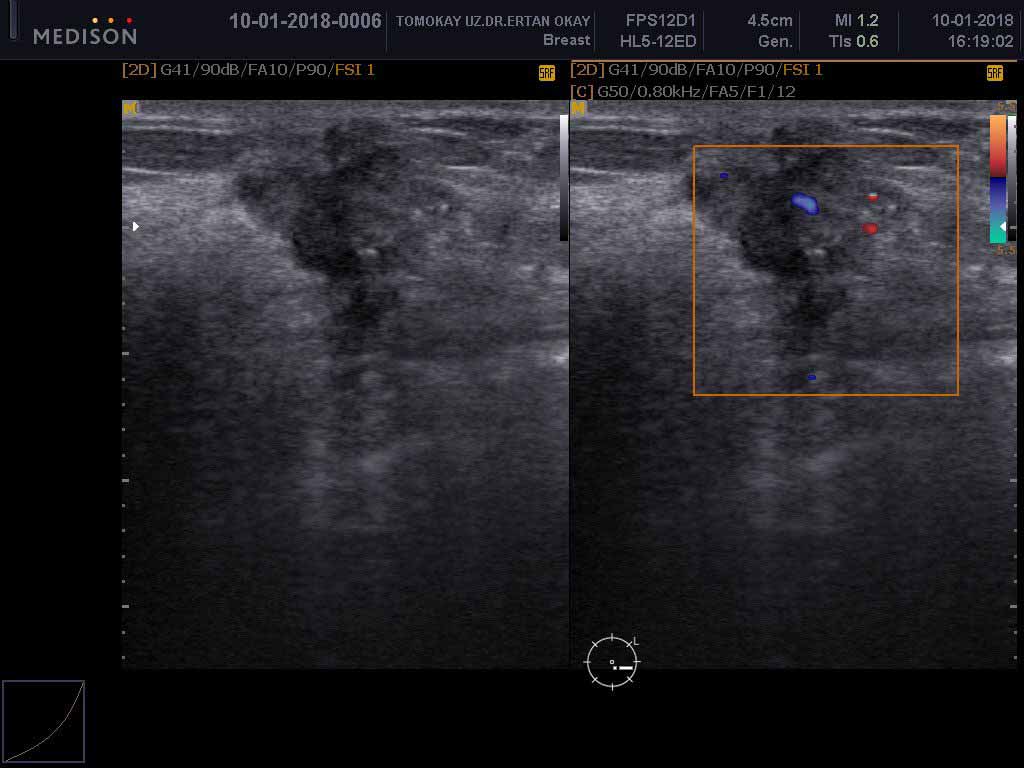

الموجات فوق الصوتية للثدي